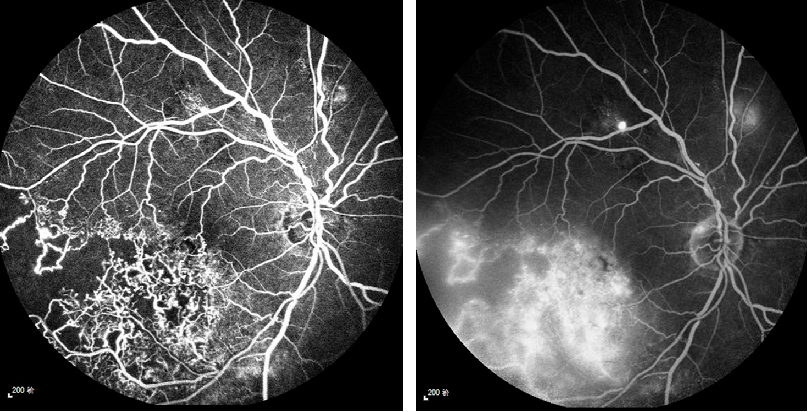

每周最佳病例分享octa全程指导下的精准视网膜光凝

图片尺寸808x412

静脉阻塞的患者,右图为视网膜的彩照,可见大量出血,左图为oct检查

图片尺寸1231x606